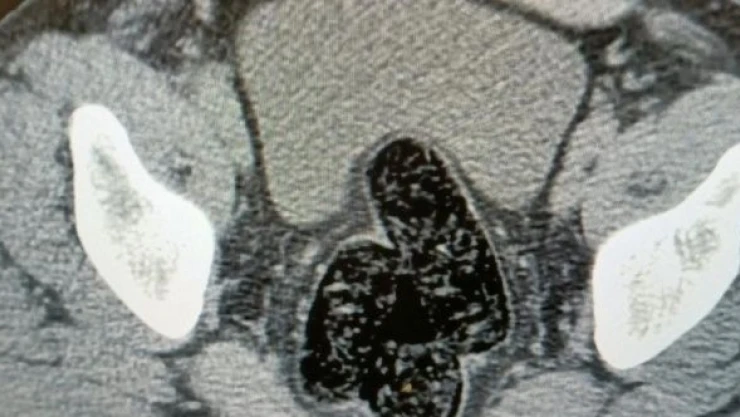

Polis ekiplerinin, Bölge Trafik Denetleme Şube Müdürlüğü önündeki uygulama noktasında dün durdurduğu ticari araçta yolculuk yapan, üzerinde ve bağırsağında 355,36 gram metamfetamin ele geçirilen M.J'nin İl Emniyet Müdürlüğü Narkotik Suçlarla Mücadele Şubesi'ndeki işlemleri tamamlandı. Sağlık kontrolünün ardından adliyeye sevk edilen zanlı, çıkarıldığı sulh ceza hakimliğince tutuklandı.